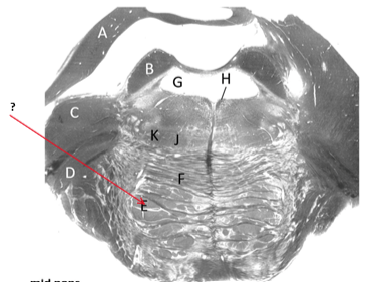

Name this and state its function.

Medial lemniscus.